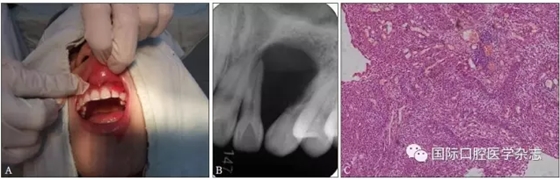

典型病例4 患者因左上頜牙齦長包塊就診,X線片檢查發(fā)現(xiàn)左上頜22—23牙區(qū)明顯的透射區(qū),邊界清楚,相鄰牙根被推擠移位。手術(shù)切除后病理結(jié)果為成釉細(xì)胞瘤(圖4)。

A:術(shù)前臨床照片;B:術(shù)前X線片;C:蘇木精-伊紅染色切片,顯示成釉細(xì)胞瘤的病理特點(diǎn) × 100。

圖 4 成釉細(xì)胞瘤

Fig 4 Ameloblastoma